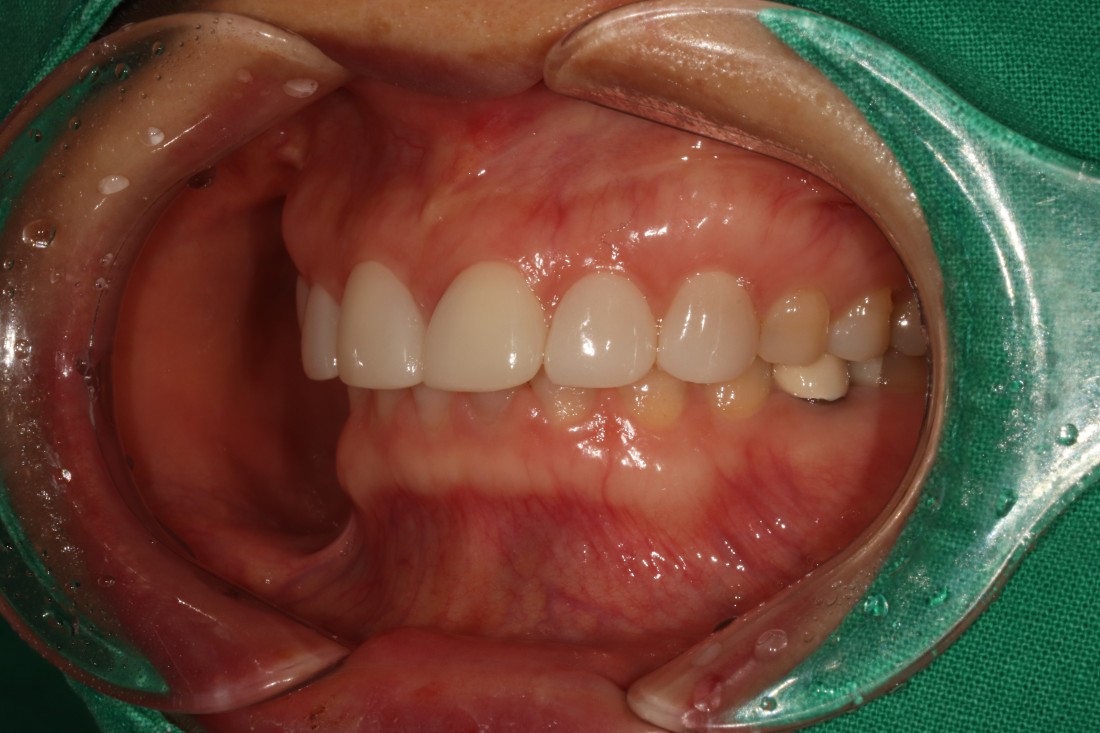

대표원장이 직접 전/후 사진을

비교하며 포스팅 해오고 있는

광주 무삭제 라미네이트

실제 사례는 위의 링크를

클릭하시면 보실 수 있습니다.

압도적인 실제 사례 케이스 건수로

증명하는 광주 무삭제 라미네이트 치과의

실력입니다.